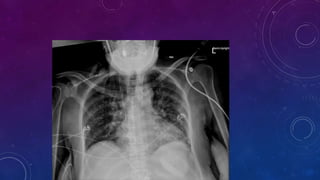

PRE RENAL TRANSPLANT EVALUATION.

WHAT ARE THE